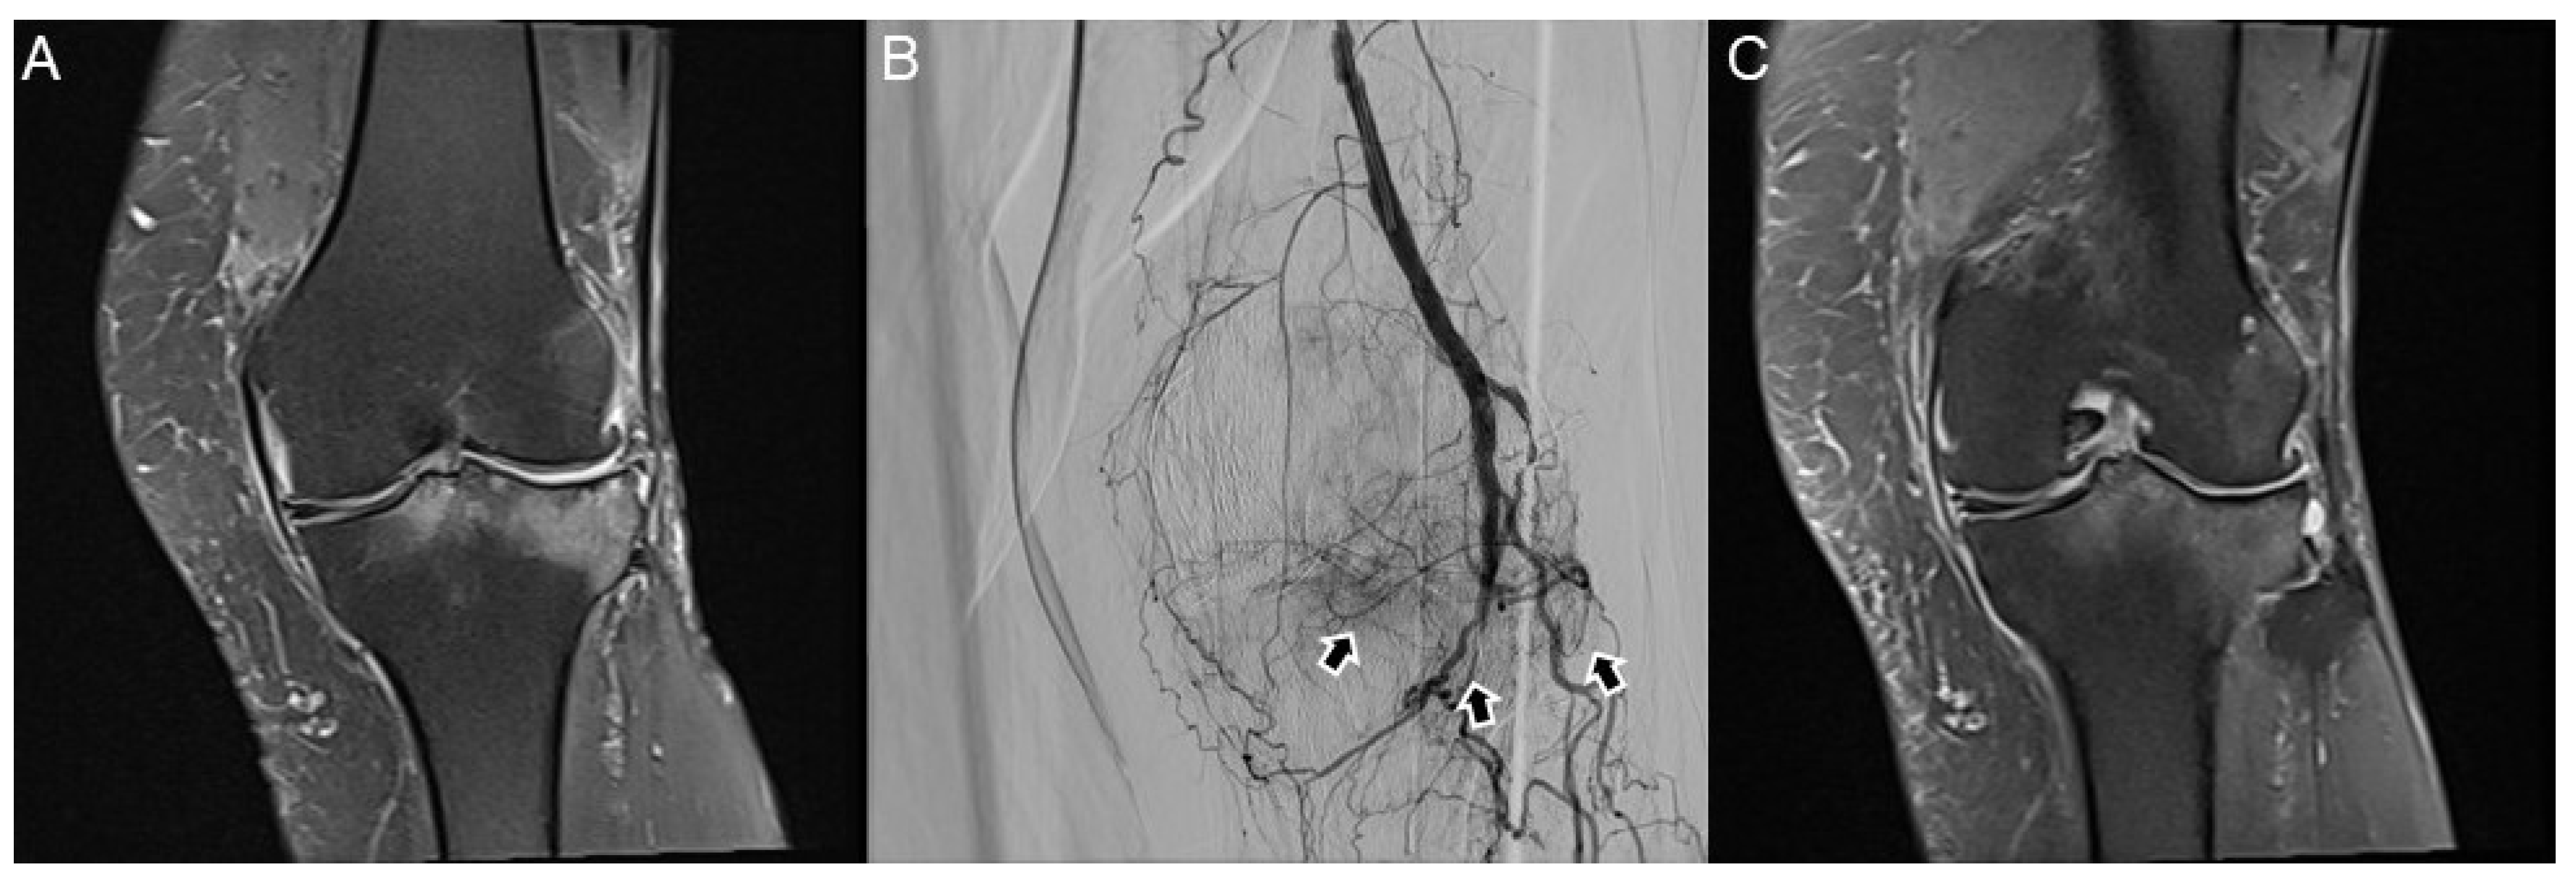

- Choi, J.W.; Ro, D.H.; Chae, H.D.; Kim, D.H.; Lee, M.; Hur, S.; Kim, H.-C.; Jae, H.J.; Chung, J.W. The Value of Preprocedural MR Imaging in Genicular Artery Embolization for Patients with Osteoarthritic Knee Pain. J. Vasc. Interv. Radiol. 2020, 31, 2043–2050. [Google Scholar] [CrossRef] [PubMed]

- Okuno, Y.; Korchi, A.M.; Shinjo, T.; Kato, S.; Kaneko, T. Midterm Clinical Outcomes and MR Imaging Changes after Transcatheter Arterial Embolization as a Treatment for Mild to Moderate Radiographic Knee Osteoarthritis Resistant to Conservative Treatment. J. Vasc. Interv. Radiol. 2017, 28, 995–1002. [Google Scholar] [CrossRef] [PubMed]

- Van Zadelhoff, T.A.; Okuno, Y.; Bos, P.K.; Bierma-Zeinstra, S.M.A.; Krestin, G.P.; Moelker, A.; Oei, E.H.G. Association between Baseline Osteoarthritic Features on MR Imaging and Clinical Outcome after Genicular Artery Embolization for Knee Osteoarthritis. J. Vasc. Interv. Radiol. 2021, 32, 497–503. [Google Scholar] [CrossRef] [PubMed]